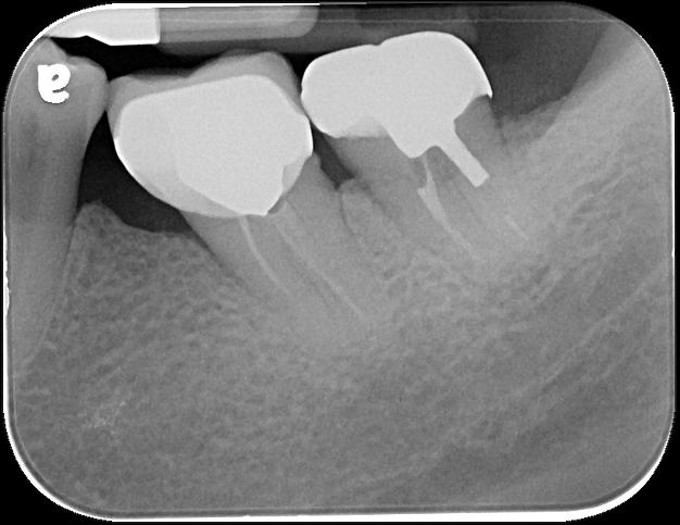

治療前,左下第二大臼齒假牙常脫落,前來求診

之前已根管治療

牙冠增長手術